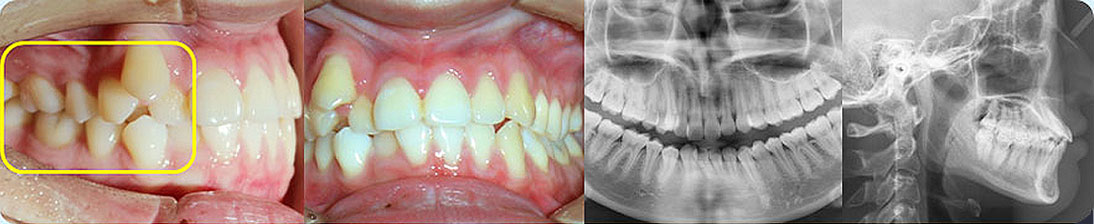

矯治采用兩種不同的厚度的膜片(牙套),發揮兩種不同膜片的各自優勢,在有效的作用時間內,矯治效率、矯治目標達成和舒適度方面較普通隱形矯正方式有明顯提升。

結合3D數字化口掃技術,可親自見證矯正后模擬效果圖

厚薄兩種矯治器,每周替換有利于牙齒位置的準確控制